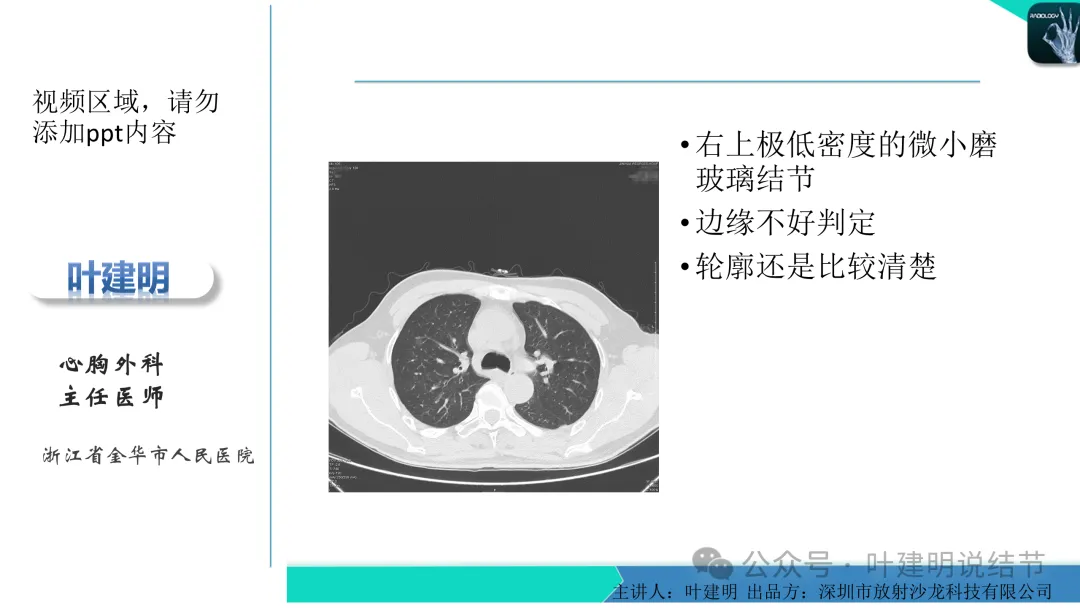

左下叶结节,轮廓稍显模糊,邻近有血管走行,无血管弯征,病灶中间密度稍低,结节密度很淡,仅小片状模糊影似的。

当地说考虑微浸润性腺癌的左下主病灶影像连续层面展示:

病灶出现,显模糊。

上图层面轮廓较清,但密度很淡,似见血管走行,但靠左前方的似条状磨玻璃密度与血管连着的到底是血管分支还是结节的一部分,其实并不确切。如果其实是血管分支,那病灶与它之间就不是空泡。

病灶在此层整体边缘显糊,灶内有空泡似的,瘤肺边界欠清。

边缘不平,还是灶内多发小空泡?邻近血管与之紧贴,但血管无异常走行。病灶密度很低,显糊。

中间所谓空泡更像是细支气管扩张,内壁非常光滑且圆形。

病灶边缘区淡而模糊。

这个病灶会是微浸润性腺癌吗?当然没有病理诊断,我也不能说百分之百必不会,但这样的病灶已经风险大到必得尽快手术切除干预了吗?显然还早着呢:1、影像不是典型的结节状;2、边缘与轮廓模糊不清;3、灶内似有细支气管扩张(更容易是细支气管扩张伴少许周围炎或肺泡上皮增生);4、血管邻近走但无牵拉影响;5、没有实性成分,没有锐利毛刺,没有胸膜牵拉,没有血管进入,没有任何倾向风险性高的影像特点。我一直强调:肺结节是否要干预处理,不要纠结于最后病理是什么,而要看风险高低;而风险高低的最重要术前判断依据一是随访有无进展,二是有没有实性成分。只要没有肉眼可见的影像上的实性成分,风险就是低的!何况病理也是人看的,原位还是微浸润,不典型增生还是原位有时也在一念之间。